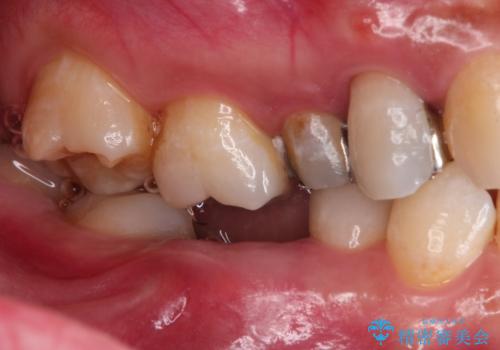

歯並びの改善とインプラントでのかみ合わせの回復 インプラント・セラミック・矯正全顎治療

- 歯医者が怖くて悪い歯をそのままにしてしまった、悪いところを治したいとのことで来院されました。

虫歯の歯や、歯を抜いてしまったところをそのまま放置していたことにより、歯並びも悪くなっていました。

矯正をはじめ、根の治療・インプラント・セラミックによる全体治療を提案させていただき、治療をしていくこととなりました。